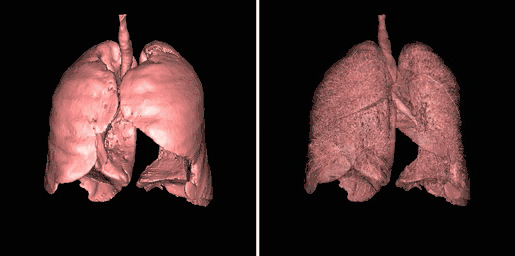

Surface rendering is also referred to as Shaded Surface Display (SSD) and involves generating surfaces from regions with similar voxel values in the 3D data as illustrated by the SPECT lung-perfusion scan shown in the left panel below:

The process involves the display of surfaces which might potentially exist within the 3D voxel data on the basis that the edges of objects can be expected to have similar voxel values. One approach is to use a grey-level thresholding technique where voxels are extracted once a threshold value is encountered in the line of the projection – see the following diagram. Triangles are then used to tesselate the extracted voxels, as shown in the right panel of the figure above – and the triangles are filled using a constant value with shading applied on the basis of simulating the effects of a fixed virtual light source – as shown in the left panel above.

An opacity table can be applied to the results so that surfaces from internal features can also be visualized. As an example, two surfaces have been identified in the following image from the CT scan where voxel values from bone surfaces are coded in an opaque yellow colour and tissue surfaces in a transparent shade of red.

A second example of using an opacity table is shown in the following figure. Here, axial CT data from the patient's airways have been segmented using a region growth technique and the result processed using surface rendering, with full opacity as shown in the left panel and with a reduced opacity (30%) as shown in the right panel:

Notice that internal features of each lung can be discerned when the opacity is reduced. Notice also that continued viewing of this type of transparency display can generate apparent reversal of the image rotation, similar to that noted for the 3D MIPs above. One method of overcoming this type of problem is to segment each lung, for instance. and to blend the results, as illustrated in the following figure: